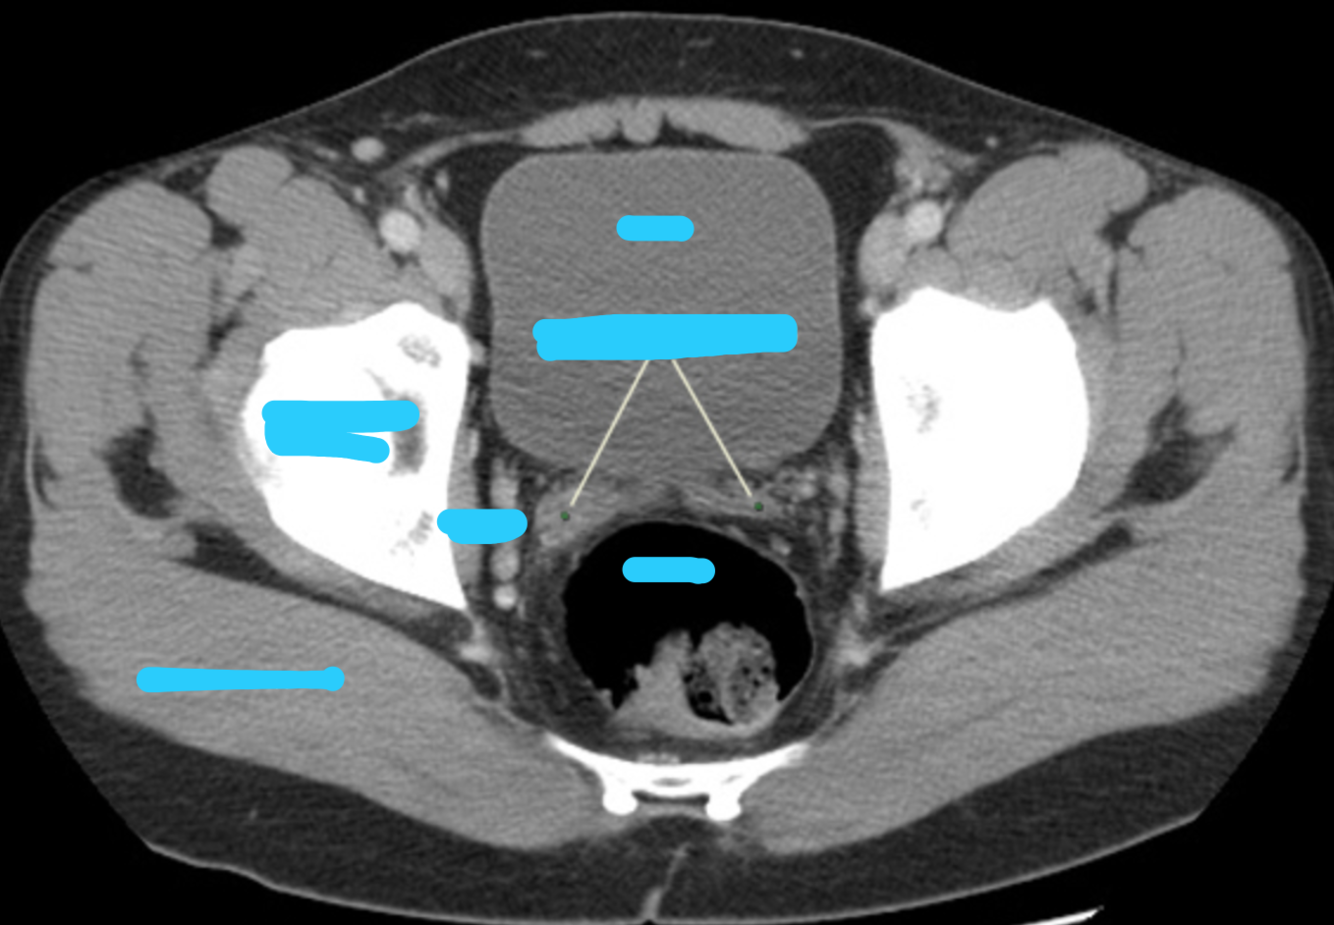

Complete labels, what is the yellow arrow pointing to?

Caclification wihtin the spermatic cord

Label & what are the yellow arrows pointing to?

Yellow arrows: vas deferens running over the external iliac vessels

Ureter passes undernea this

running superior to seminal vesicles

(CT axial of male pelvis)